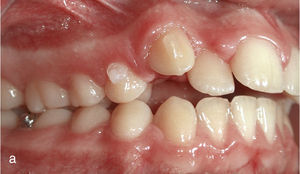

El paciente se presentó en nuestro centro con el siguiente cuadro: dentición permanente con proinclinación de dientes anteriores y desviación de la línea media, diente 53 persistente, dientes 13 y 23 elevados y desplazados hacia vestibular, curva de Spee marcada con extrusión del sector anteroinferior, dientes rotados y apiñados en maxilar y mandíbula, clase II de Angle con un resalte de 4mm y sobremordida de 0mm, además de ausencia de guía canina (figs. 13a a 13c y 14a a 14e).

El plan de tratamiento incluyó el establecimiento de una clase I de Angle con sobremordida horizontal y vertical fisiológicas mediante la distalización del sector posterosuperior, con corrección de los caninos superiores y aseguramiento de una guía canina. Las arcadas se dotaron además de una apariencia armoniosa eliminando la giroversión y los apiñamientos mediante la reducción del esmalte interproximal y el ajuste de las líneas medias. El paciente optó por un tratamiento con el sistema Invisalign alternativo a la aparatología fija con brackets. Se colocó un atache rectangular vertical en los dientes 13 y 23 y, en el curso del tratamiento, también en los dientes anterosuperiores y en el diente 43. Además durante todo el tratamiento el paciente llevó elásticos de clase II en ambos lados, del diente 14 al diente 46 y del diente 24 al diente 36 para obtener el anclaje necesario durante la distalización. La figura 15 muestra la situación intraoral de un caso similar con brackets en los dientes 13 y 46. En la zona de los brackets se acortó el alineador. Además de los alineadores se utilizaron elásticos de clase II del diente 13 al diente 46.